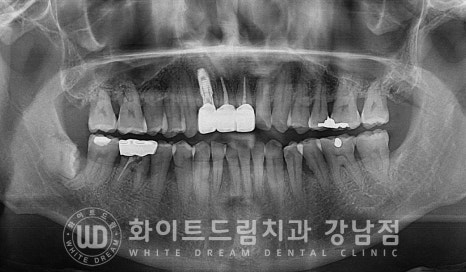

환자분은 초기 11번 치아가 뒤로 물리는 반대교합 형태를 가지고 계셨는데요.

이번에 보철치료를 진행하면서 이 반대교합도 정상교합으로 되돌려드렸답니다.

환자분의 치료 기간은 23.03.16 - 23.08.07으로

5개월 정도의 치료 기간이 소요되었습니다.

치료를 진행하는 과정에서 정기적으로 잇몸치료도 함께 진행해 드려

치료를 마무리하는 시점에는 잇몸상태도 많이 호전된 상태인 것이 확인됩니다.